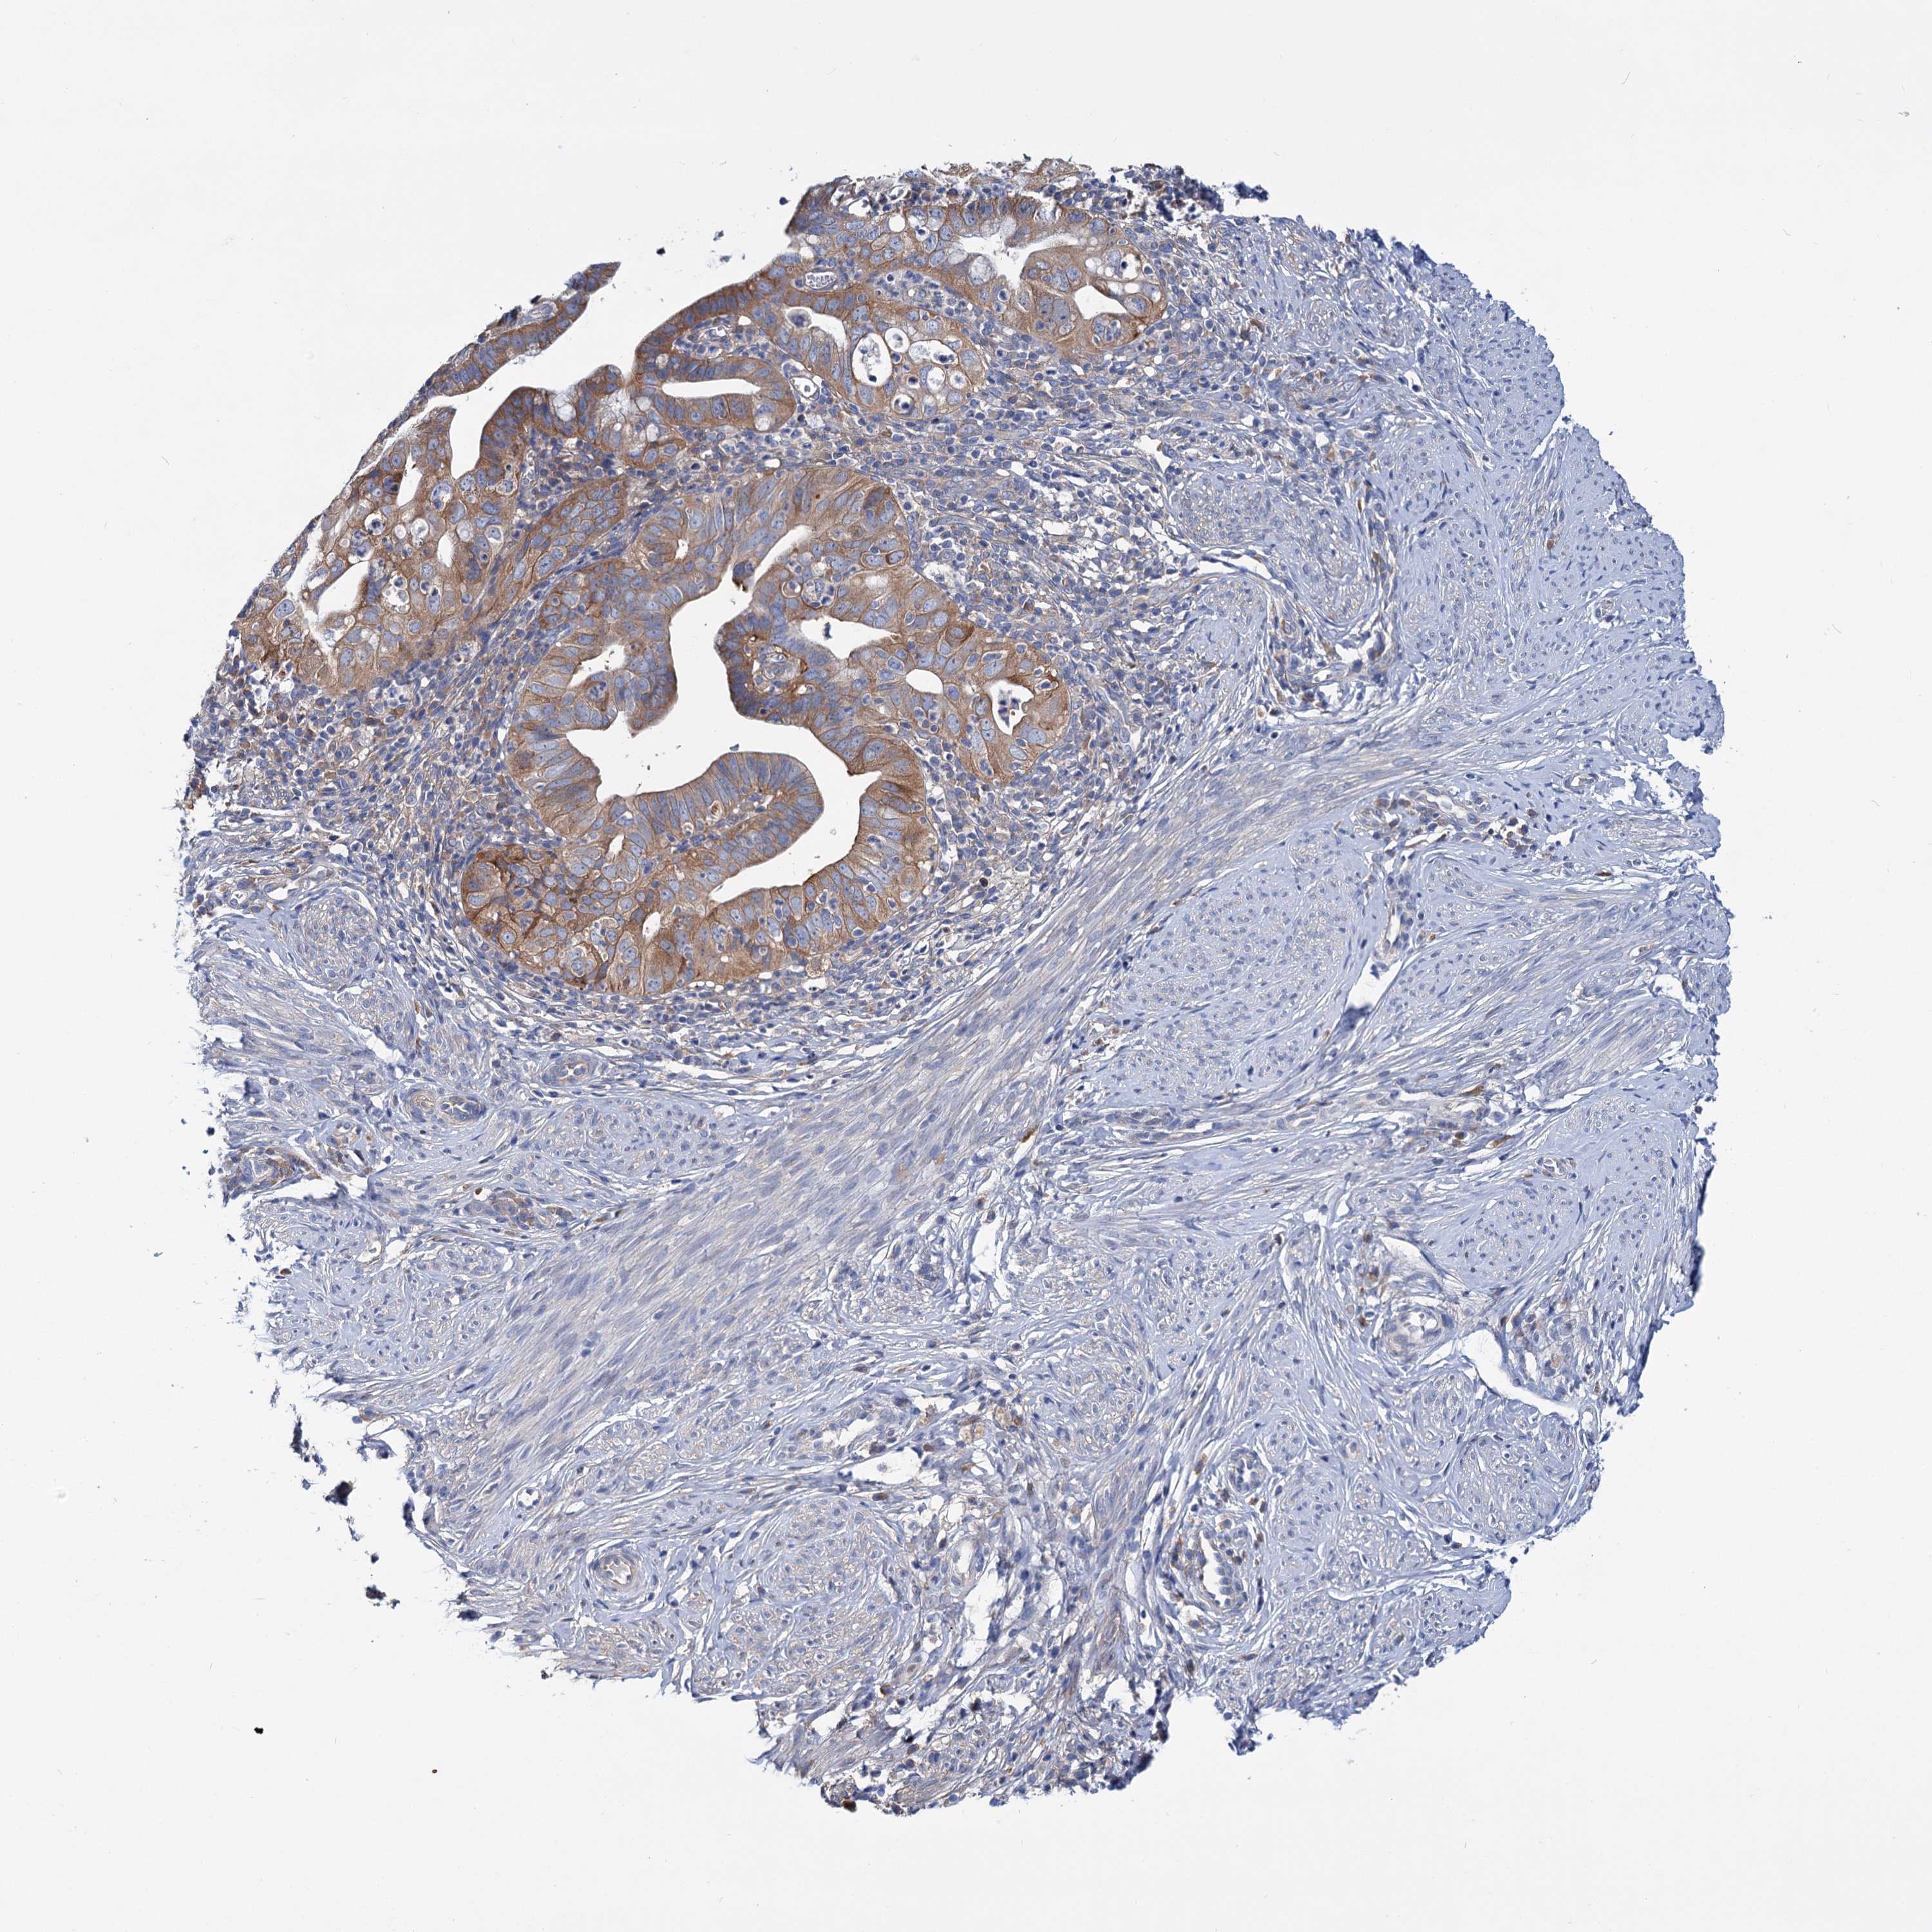

CERVICAL CANCER - Protein expressioni

A mouse-over function shows sample information and annotation data. Click on an image to view it in a full screen mode. Samples can be filtered based on level of antibody staining by selecting one or several of the following categories: high, medium, low and not detected. The assay and annotation is described here.

Note that samples used for immunohistochemistry by the Human Protein Atlas do not correspond to samples in the TCGA dataset.

Antibody stainingi

Antibody staining in the annotated cell types in the current human tissue is reported as not detected, low, medium, or high, based on conventional immunohistochemistry profiling in selected tissues. This score is based on the combination of the staining intensity and fraction of stained cells.

Each image is clickable and will lead to virtual microscopy that enables deeper exploration of all samples and also displays staining intensity scores, fraction scores and subcellular localization as well as patient and tissue information for each sample.

Antibody HPA038793

Antibody HPA053691

Staining

High

Medium

Low

Not detected

Intensity

Strong

Moderate

Weak

Negative

Quantity

>75%

75%-25%

<25%

None

Location

Nuclear

Cytoplasmic/membranous

Cytoplasmic/membranous,nuclear

Squamous cell carcinoma, NOS

Adenocarcinoma, NOS